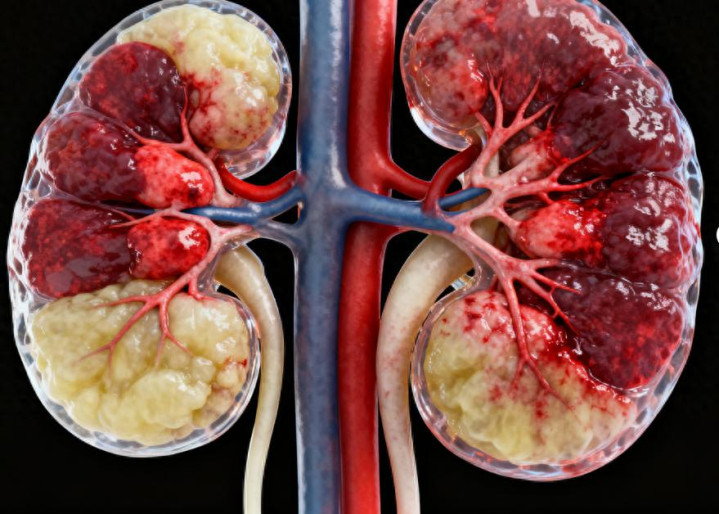

肾脏是东谈主体的 “排毒过滤器”,沉默处理代谢废料和饱和水分,可它的 “报警形势” 经常很避讳,容易被咱们当成小时弊忽略。尤其所以下 3 个异常信号,一朝出现,千万别硬扛,可能是肾脏急症的前兆。

第一个信号是排尿出现 “反常”。平方成年东谈主每天尿量约略在 1500-2000 毫升,排尿顺畅、尿色呈淡黄色。要是短暂出现 24 小时尿量少于 400 毫升(差未几小半瓶矿泉水),以至不足 100 毫升,或是通顺几小时无尿,就属于异常情况。除此以外,尿色短暂变深,像浓茶、酱油一样,或是尿液中泡沫增多,且泡沫永劫期不用散,皆可能是肾脏出了问题。好多东谈主会以为 “尿量少即是喝水不够”,拚命补水却不见完毕,殊不知这可能是急性肾衰、肾小球病变或尿路封闭的信号,捏续不缓解会加剧肾脏毁伤。

第二个信号是不解原因的 “坚毅浮肿”。偶尔熬夜后眼睑浮肿、久站后小腿发胀,休息后能快速消退,这属于生感性浮肿,无需过度惦记。但要是浮肿变得 “坚毅”—— 先是眼睑、面部浮肿,自由扩张到作为,以至全身皆肿,按压浮肿部位后会留住凹下,半天皆不规复,就必须警惕肾源性浮肿。这是因为肾脏排水智力下跌,饱和的水分和钠在体内堆积,导致组织水肿。这种浮肿和凡俗 “胖” 实足不同,经常随同体重尴尬增多,即便禁止饮食、减少饮水,也很难改善,背后可能荫藏惊愕性肾衰、肾病玄虚征等急症。

第三个信号是全身尴尬的 “不适感”。肾脏出问题后,体内的毒素无法实时排出,会影响全身多个器官。比如短暂出现的捏续疲倦,稍稍活动就累得喘不外气,连寝息皆缓解不了;或是毫无征兆的恶心、吐逆、食欲变差,吃不下饭还总以为胃部不适。这些症状很容易被当成 “肠胃病”“伤风”,但其实是肾脏毒素堆积激发的全身反映。此外,部分东谈主还会出现头晕、血压短暂升高,这亦然肾脏功能异常的蜿蜒进展,若不足时干预,可能诱发心衰等更严重的并发症。